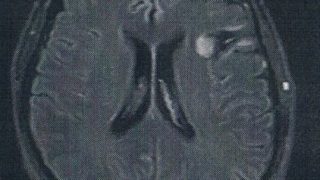

GLIOMA:手術後138ヶ月目の検査

手術から11年が経過した。半年ごとの定期検査です。検査概要びまん性星細胞腫グレード2(悪性転化しやすい腫瘍)MRI検査: 造影剤なし / 造影剤あり造影剤ありの場合:4時間前から絶食し、MRIの1時間前に血液検査を済ませる。診断結果前回のM...